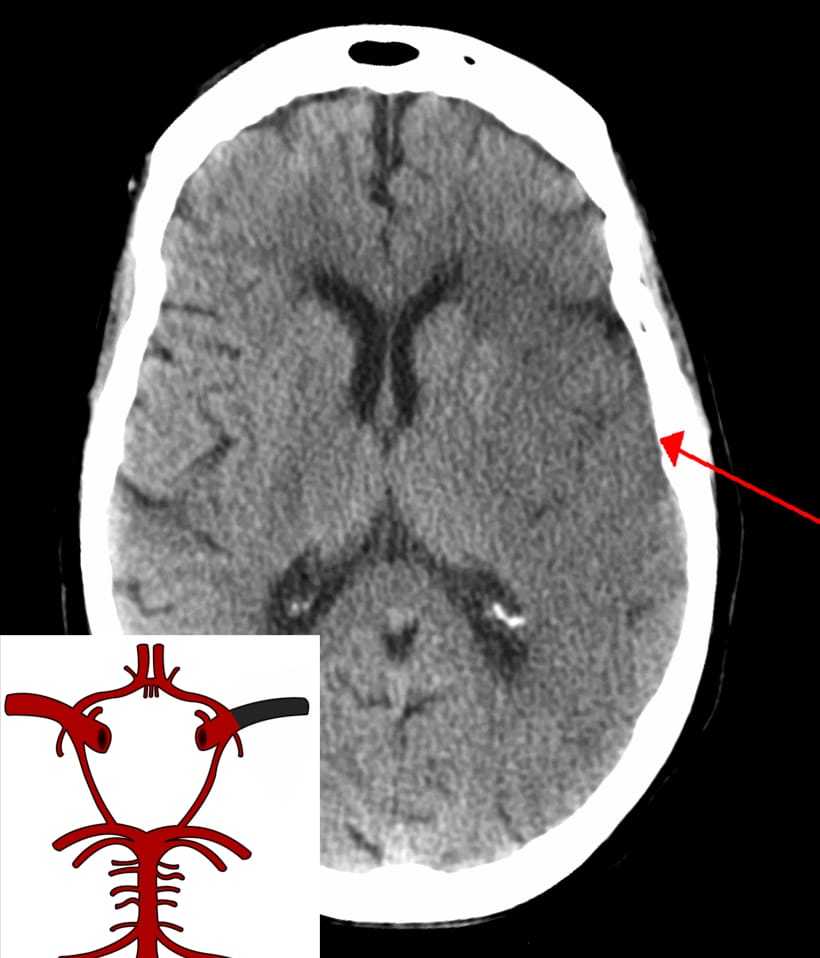

What stroke is shown in the image?

Intracerebral haemorrhage.

Subarachnoid haemorrhage.

Ischaemic stroke specifically total anterior circulation stroke (TACS).